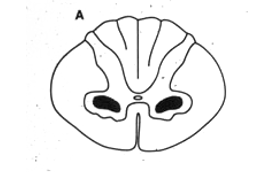

Subacute Degeneration of the cord